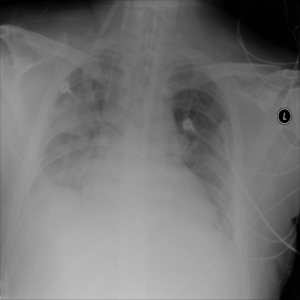

Anomaly detection is the problem of recognizing abnormal inputs based on the seen examples of normal data. Despite recent advances of deep learning in recognizing image anomalies, these methods still prove incapable of handling complex medical images, such as barely visible abnormalities in chest X-rays and metastases in lymph nodes. To address this problem, we introduce a new powerful method of image anomaly detection. It relies on the classical autoencoder approach with a re-designed training pipeline to handle high-resolution, complex images and a robust way of computing an image abnormality score. We revisit the very problem statement of fully unsupervised anomaly detection, where no abnormal examples at all are provided during the model setup. We propose to relax this unrealistic assumption by using a very small number of anomalies of confined variability merely to initiate the search of hyperparameters of the model. We evaluate our solution on natural image datasets with a known benchmark, as well as on two medical datasets containing radiology and digital pathology images. The proposed approach suggests a new strong baseline for image anomaly detection and outperforms state-of-the-art approaches in complex medical image analysis tasks.

翻译:异常检测是根据正常数据实例识别异常输入的问题。尽管在识别图像异常方面最近取得了深层次学习的进展,但这些方法仍然证明无法处理复杂的医学图像,如胸部X光几乎看不到异常和淋巴节点转移等。为了解决这一问题,我们引入了一种新的强有力的图像异常检测方法。它依靠古典的自动解剖器方法,经过重新设计的培训管道来处理高分辨率、复杂图像和图像异常分数。我们重新审视了完全不受监督的异常点检测的非常问题说明,在模型设置期间,根本没有提供异常的例子。我们提议放松这一不现实的假设,仅使用少量有限的异常点来开始搜索模型的超参数。我们评估我们使用已知基准的天然图像数据集以及包含放射学和数字病理图像的两个医疗数据集的解决方案。拟议方法为在复杂的医学图像分析任务中,为图像异常点检测和超常规状态方法提供了新的强基线。